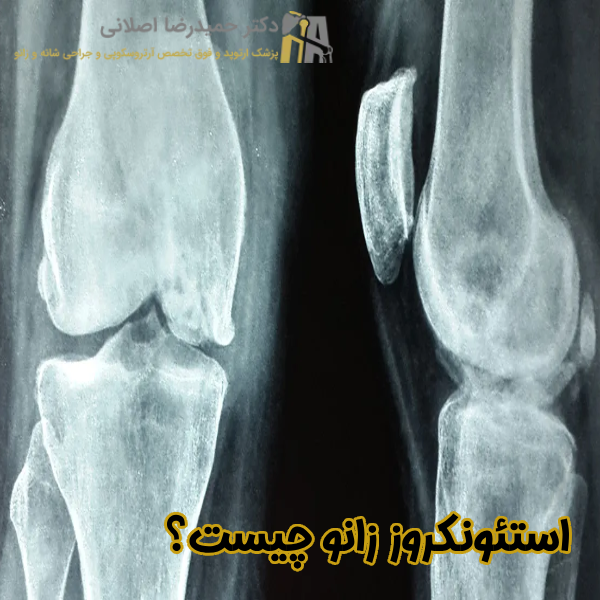

استئونکروز زانو چیست؟

استئونکروز زانو یا نکروز آواسکولار یکی از بیماری های مفصلی بوده که به دلیل کاهش خونرسانی و اکسیژن رسانی به استخوان زیر غضروفی در زانو بروز می کند. این اختلال منجر به مرگ سلولی و تحلیل استخوان ها شده و معمولا با درد شدید، تورم و محدودیت حرکتی همراه است. عوامل متعددی اعم از آسیب های تروماتیک، بیماری های عروقی و مصرف برخی داروها در بروز این بیماری نقش بسزایی دارند.